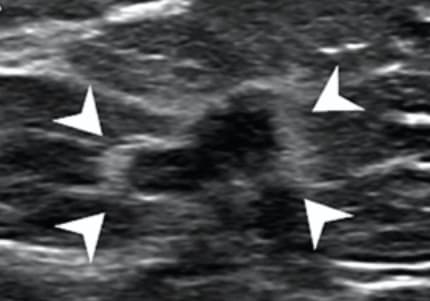

La 6ème édition de BI-RADS pourrait s'enrichir d'un nouveau critère

La présence d'une bande hyperéchogène entourant une masse mammaire suspecte à l'échographie pourrait constituer un indicateur supplémentaire de malignité mammaire. C’est ce que montre une étude publiée dans l’American Journal of Roentgenology (AJR) qui objective des associations significatives aux c...